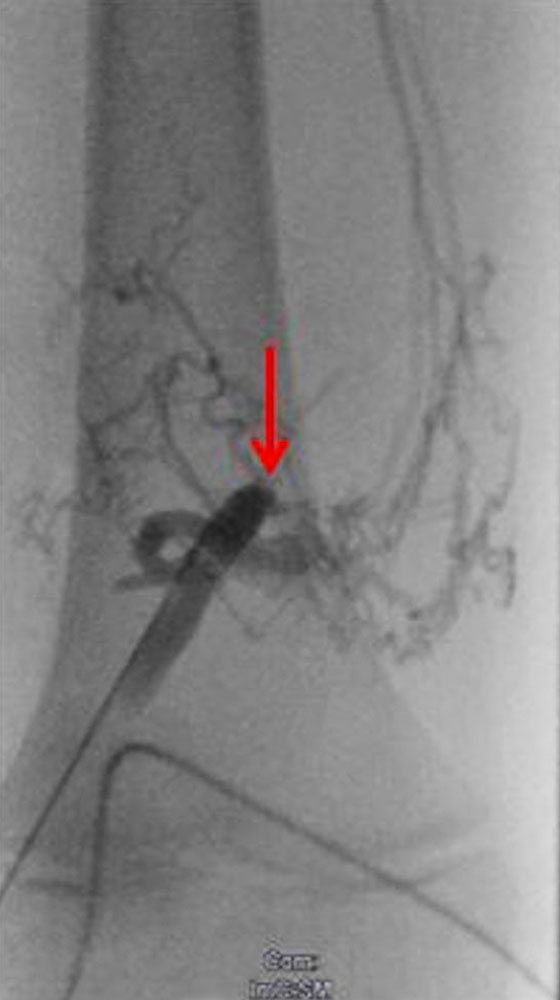

In women, the labium majus (usually on one side, more rarely on both sides) is often affected together with the ipsilateral leg, especially in the case of extensive venous or lymphatic malformations. In these cases, painful thrombophlebitis is more frequent, with increased swelling/increased volume, especially in connection with menstruation. Large thrombophlebitis can also lead to sometimes large local painful swellings, which then impair sexual function and are painful when sitting or riding a bicycle. For women, therefore, invasive therapy with sclerotherapy is more likely to be indicated. Since resection operations can cause local sensitivity disorders and also significant bleeding, this is a domain of sclerotherapy, which can be performed with good results. It is important to take a proper history that also includes this problem because patients are less likely to report this themselves.